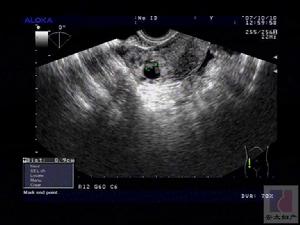

21例停經49~71d平均(55±3.5)d;伴有噁心嘔吐等早孕反應5例;下腹部隱痛4例;少量陰道流血6例;婦檢:宮角一側增大者15例;腹部檢查均無移動性濁音;輔助檢查:尿人絨毛膜促性腺激素(hCG)陽性16例,弱陽性1例,血hCG檢查4例,分別為4,500、6,800、10,200、11,200U/L;B超:子宮內近子宮角處見孕囊或見液性暗區的強回聲光團,遠離宮腔線,該側子宮角膨大、隆起,即孕囊位於宮角部16例;子宮稍大、宮內外均未見孕囊4例,結合病史,4例患者均有停經、腹痛及陰道流血,婦科檢查均宮角一側增大,血hCG均>5,000U/L,為明確診斷故準備行宮腔鏡檢查;1例人流術前B超提示宮內孕,但人流時未見絨毛,為排除人流時漏吸故行宮腔鏡檢查。診斷標準

孕8周前的宮角妊娠與宮內妊娠較難區別,婦科檢查子宮增大與停經天數相符,但一側宮角部明顯較軟,B超檢查對宮角妊娠可較清楚地辨認,子宮增大、一角突出,其中可見妊娠環或胚胎,宮腔內無妊娠物。只有在做流產治療前仔細地排除宮角妊娠,才可儘量避免發生人為地引起異位妊娠破裂,甚至發生死亡的悲劇。